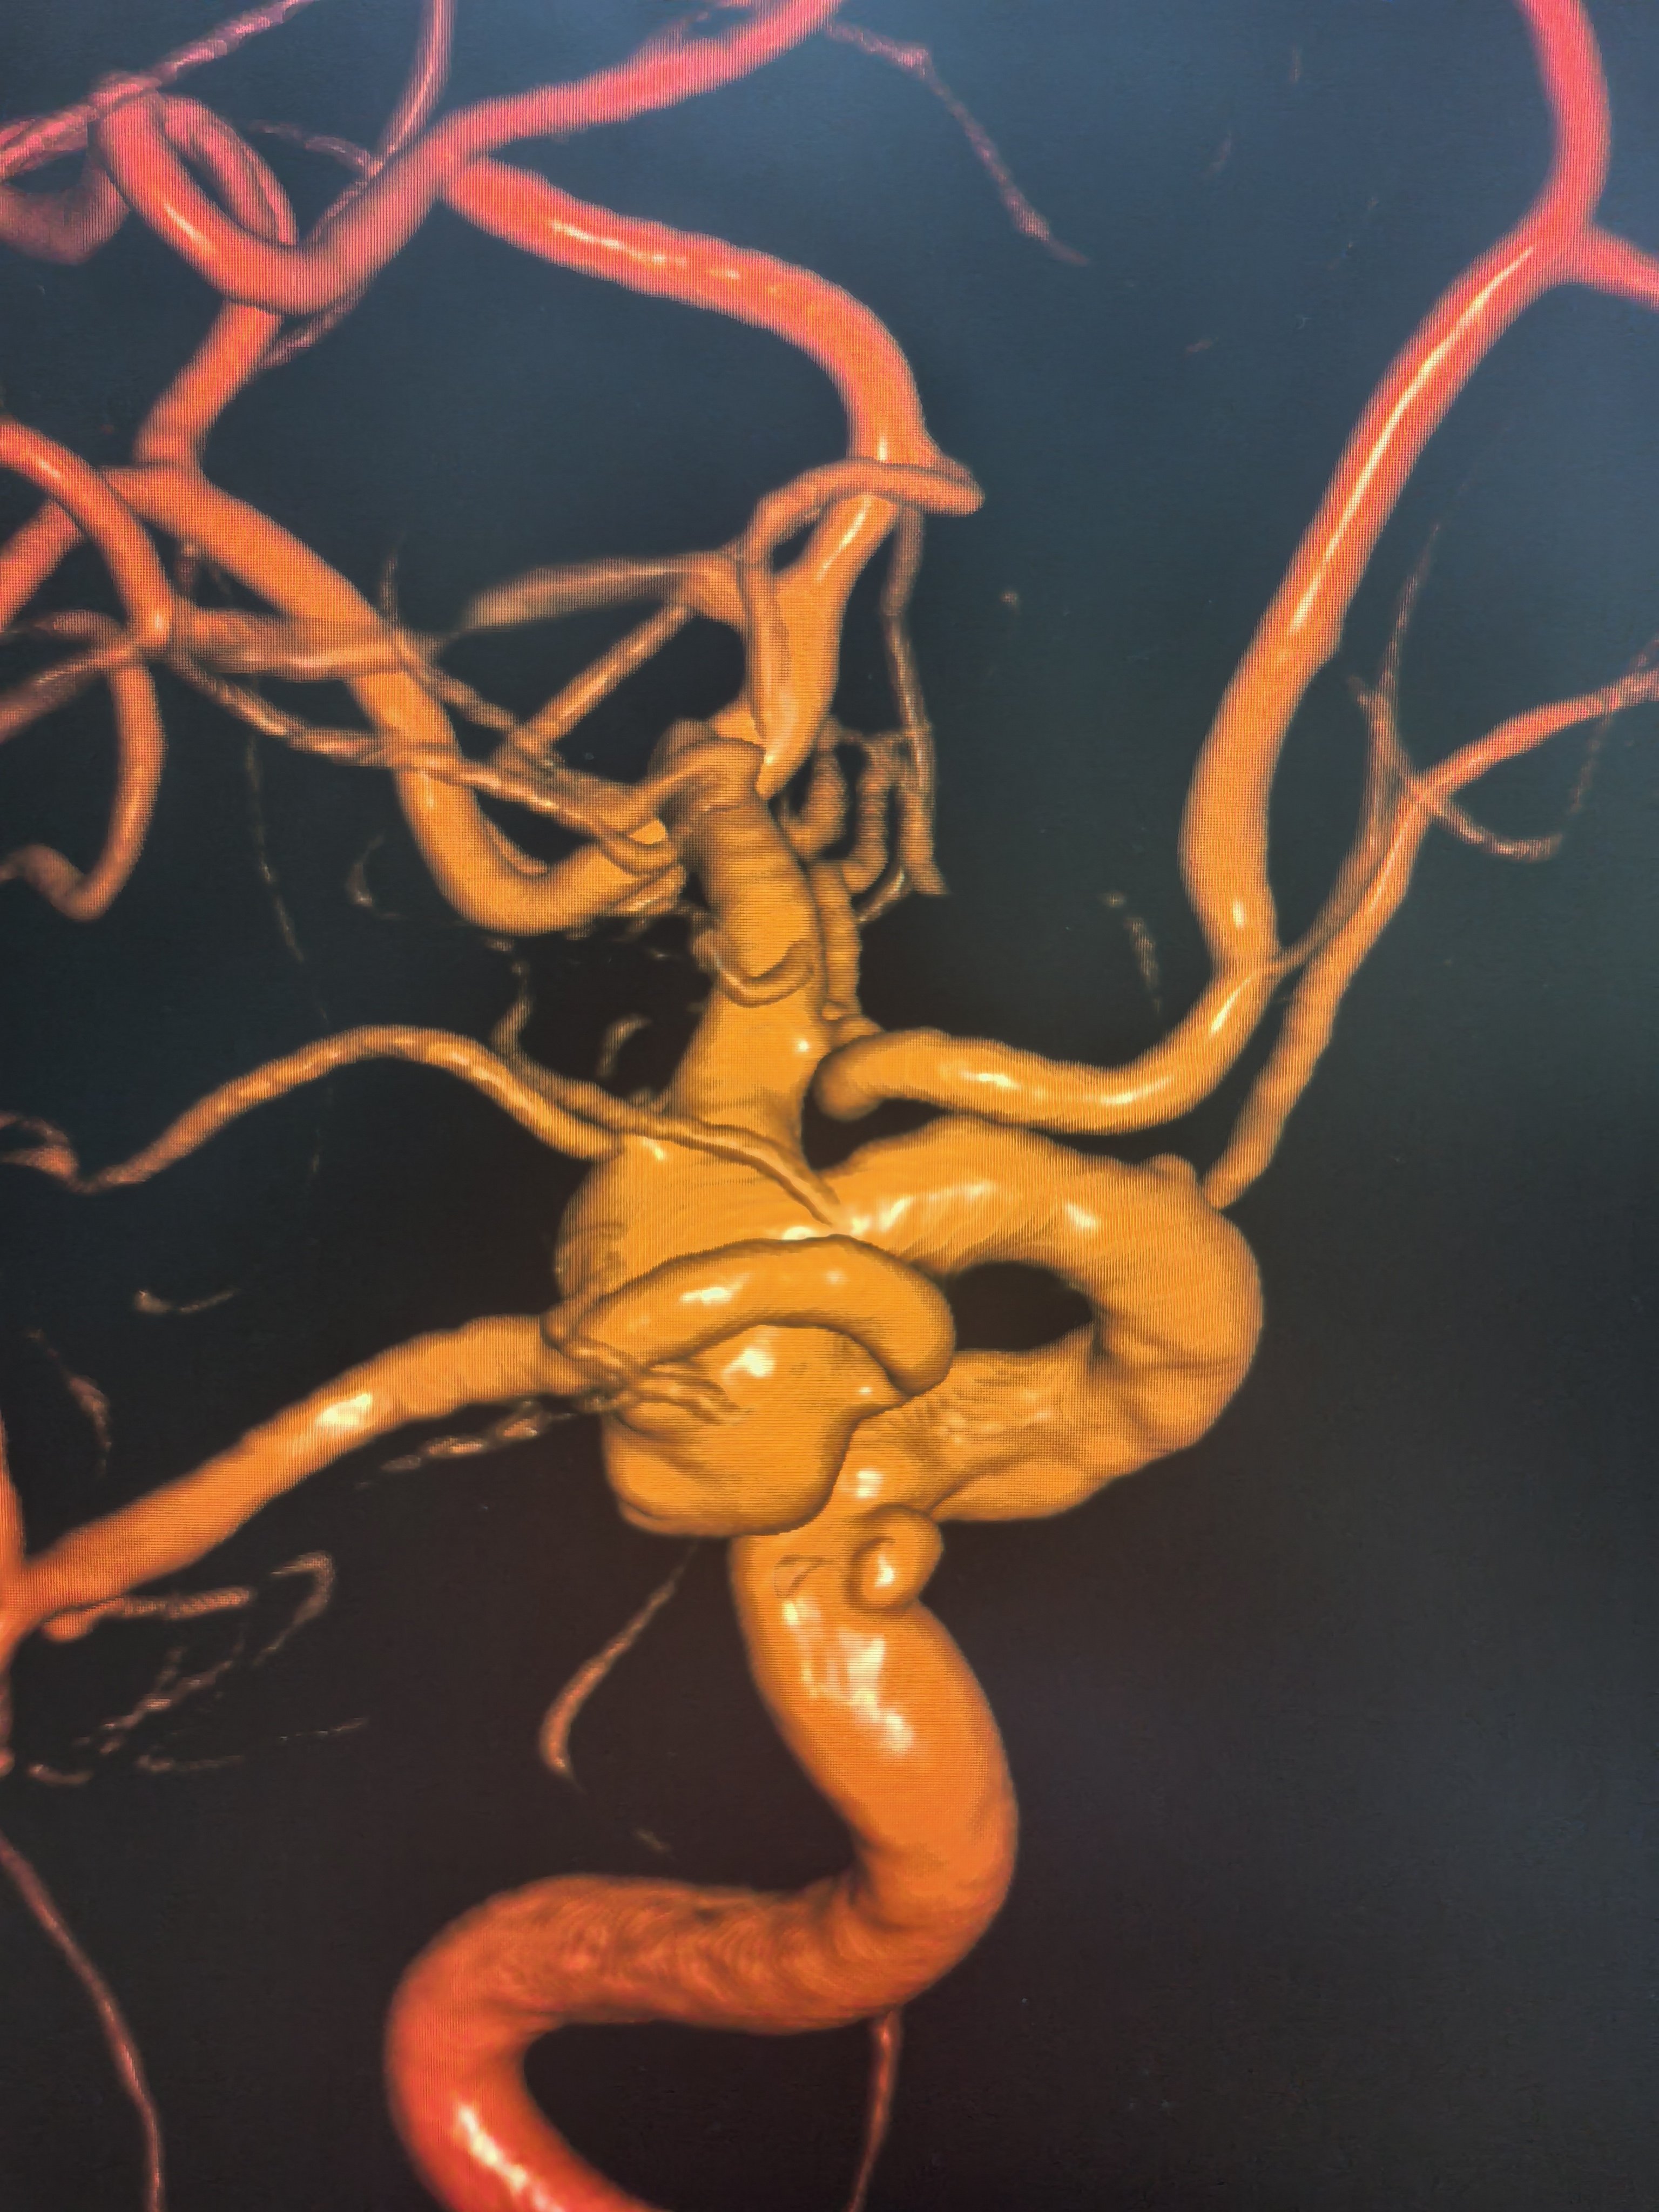

三维旋转造影!

三维重建,胚胎型大脑后动脉发自瘤体侧壁,超选困难且风险大!